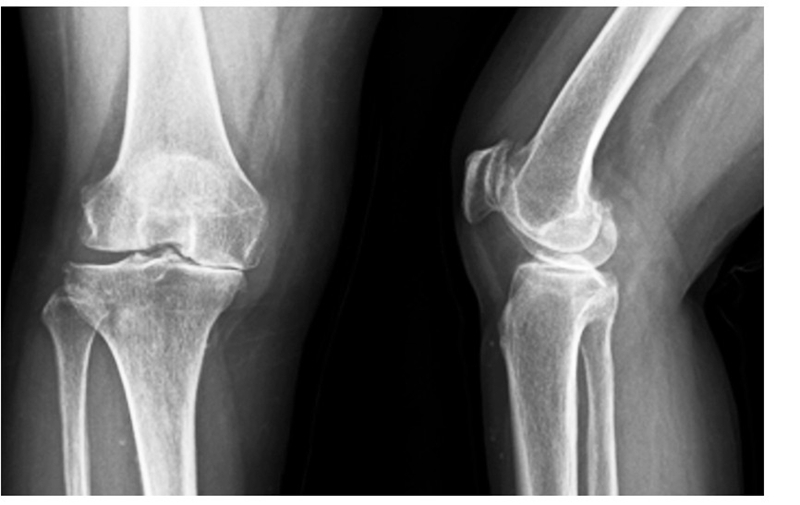

(2)65岁女性患者,以右膝关节疼痛3年、加重半年为主诉入院,入院查体右下肢内翻畸形8°,膝关节内侧间隙压痛阳性,外侧无压痛,浮髌试验阴性,髌骨研磨试验 阴 性,抽 屉 试 验 阴 性,ROM10°~130°,诊断为右膝关节前内侧骨关节炎,行 Oxford活 动 平 台 内 侧 单髁置换术。术后24h内间断 冰 敷,给予预 防 感 染、消 肿 止 痛及抗凝 治 疗,术 后24h康复师指导助行器辅助下床活动,术后1个月膝关 节 HSS评 分 由62分升至81分,KSS评 分 由50分升至85分,内侧疼痛消失,手术效果良好。手术前后影像学资料见图3~4。

图3术前 X线片示内侧间隙呈骨对骨改变

图4术后 X线片示假体位置良好,大小合适,活动垫片在位